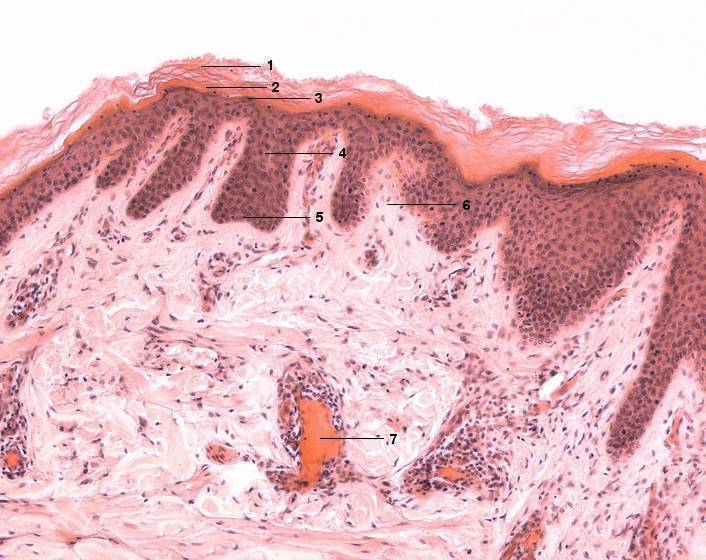

1 Stratum corneum

2 Stratum lucidum

3 Stratum granulosum

4 Stratum spinosum

5 Stratum basale

6 Corium, Papille des Stratum papillare

7 Venenanschnitt